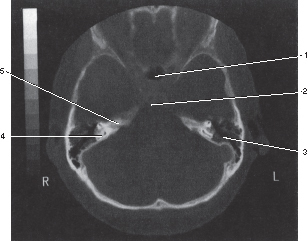

Number 1 corresponds to which of the following?

Posterior clinoid process

Number 4 corresponds to which of the following?

Semicircular canal

5

Petrous bone

Q

Sphenoid sinus